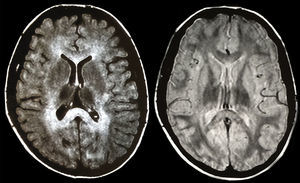

Se realizó una Resonancia Magnética Nuclear (RMN) craneal, informada como leucoencefalopatía metacromática, que puso de manifiesto una extensa afectación de la sustancia blanca cerebelosa y cerebral subcortical, de los centros semiovales, cápsulas internas, externas y ambos branchium pontis (fig. 1). En un estudio de potenciales evocados auditivos y visuales, se halló una alteración de la conducción entre oliva bulbar y protuberancia, y una importante alteración de las vías visuales a nivel retroquiasmático, respectivamente. El EEG fue informado como normal y no existía enfermedad a nivel de los nervios periféricos. La valoración psiquiátrica descartó psicopatología primaria y emitió el diagnóstico de síndrome frontal en el contexto de trastorno orgánico.

Con el diagnóstico de leucoencefalopatía, ataxia por gluten (AG), EC y déficit de IgA, se inició tratamiento con suplementos de hierro y ácido fólico asociados a dieta sin gluten, con buena adherencia por parte de la paciente, corrigiéndose las alteraciones conductuales y desapareciendo el temblor y la ataxia al cabo de un año. La RMN craneal de control a los 2 años del diagnóstico demostró remisión de las lesiones descritas. Igualmente, se ha comprobado normalización histológica, serológica e inmunofenotípica de los marcadores de EC.